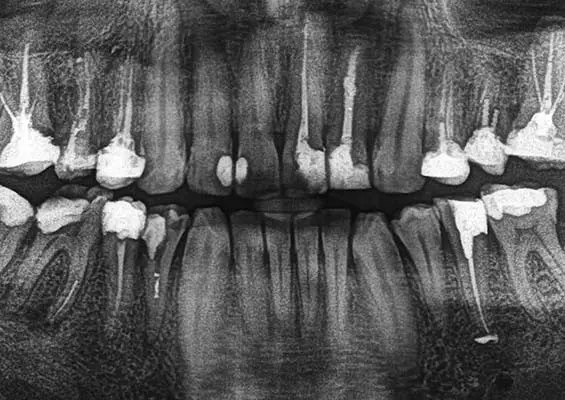

W tym wydaniu m.in: zapalenie przyzębia a ryzyko otępienia, gojenie zmian okołowierzchołkowych, okolica przyszyjkowa jako kompleksowe spojrzenie kliniczne, WawaDent 2024, by-pass złamanego narzędzia.